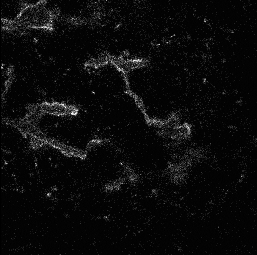

Motivated by the challenging segmentation task of pancreatic tubular networks, this paper tackles two commonly encountered problems in biomedical imaging: Topological consistency of the segmentation, and expensive or difficult annotation. Our contributions are the following: a) We propose a topological score which measures both topological and geometric consistency between the predicted and ground truth segmentations, applied to model selection and validation. b) We provide a full deep-learning methodology for this difficult noisy task on time-series image data. In our method, we first use a semisupervised U-net architecture, applicable to generic segmentation tasks, which jointly trains an autoencoder and a segmentation network. We then use tracking of loops over time to further improve the predicted topology. This semi-supervised approach allows us to utilize unannotated data to learn feature representations that generalize to test data with high variability, in spite of our annotated training data having very limited variation. Our contributions are validated on a challenging segmentation task, locating tubular structures in the fetal pancreas from noisy live imaging confocal microscopy. We show that our semi-supervised model outperforms not only fully supervised and pre-trained models but also an approach which takes topological consistency into account during training. Further, our approach achieves a mean loop score of 0.808 for detecting loops in the fetal pancreas, compared to a U-net trained with clDice with mean loop score 0.762.